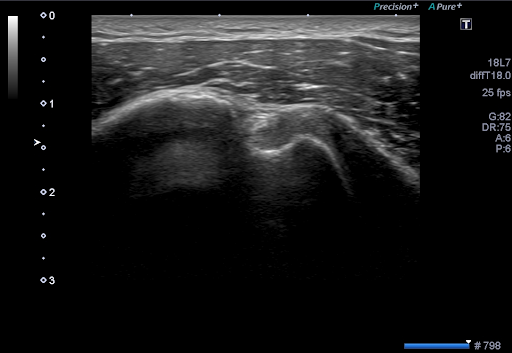

Технология Precision Imaging улучшает определение границ и делает края структур более четкими.

Технология ApliPure+ позволяет достигать беспрецедентной однородности и детализации при сохранении клинически значимых маркеров.

Real-time Elastography*

Эластография в реальном времени обеспечивает цветовое картирование, отражающее деформацию тканей и их эластичность после компрессии. Данная технология необходима для четкой локализации и оценки пальпируемых массы с исключительной точностью, чувствительностью и воспроизводимостью.